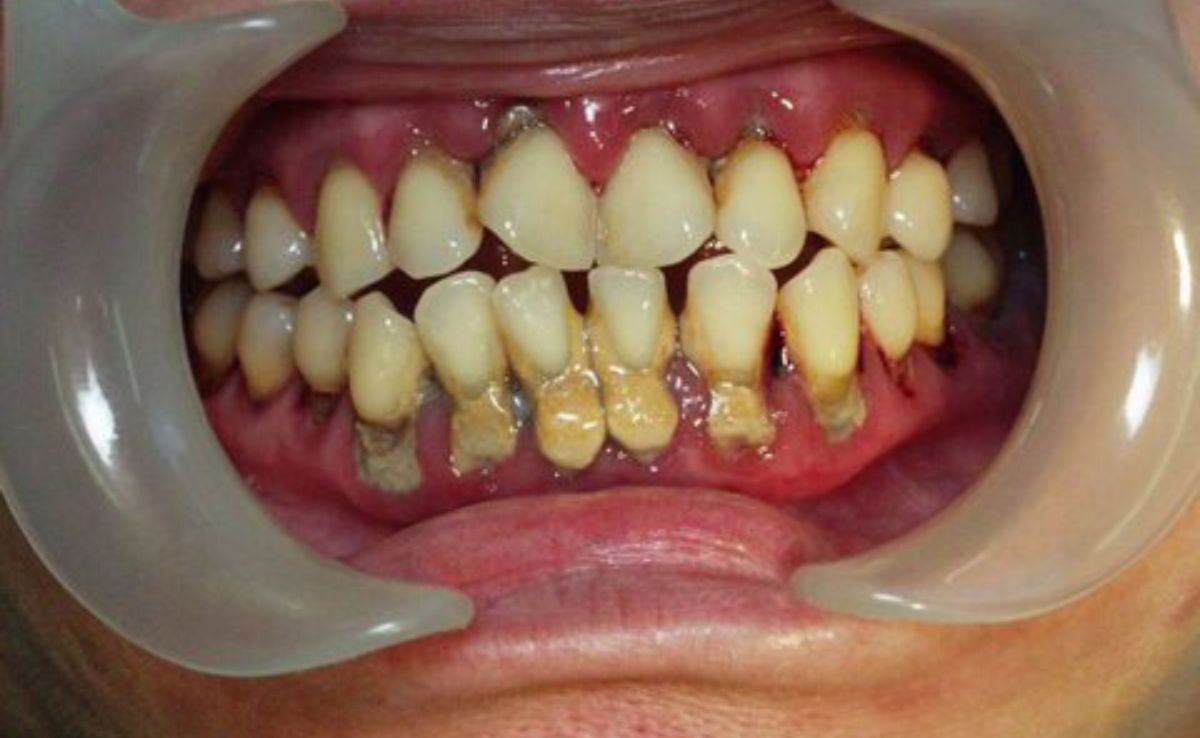

When a tooth is too damaged from decay or trauma to be saved, extraction becomes necessary. We offer both simple and surgical extractions, depending on the position and condition of the tooth.

Oral and maxillofacial surgery may be necessary when your condition involves more than just the teeth, particularly the jaw, facial structure, or surrounding soft tissues. Some common situations where this surgery might be recommended include: